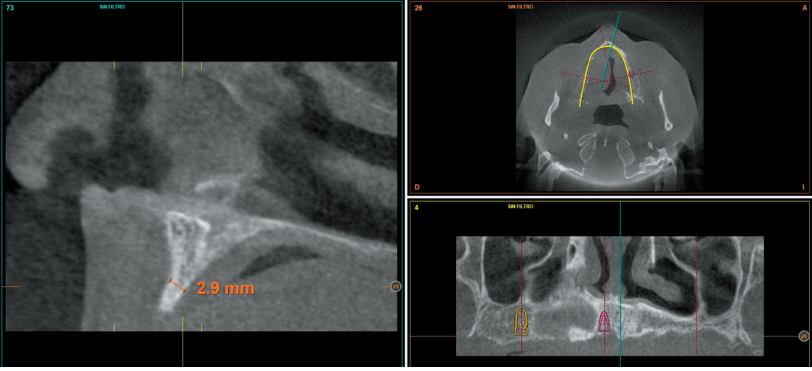

Subsequently, we proceed to perform a dental cone beam that offers a more accurate view of the type of implant rehabilitation that can be proposed. In the sections corresponding to the upper maxilla, there are areas where the direct insertion of the implants can be performed such as those corresponding to 16 and the central incisor zone of this quadrant (Figures 4-5) or in the second quadrant the area of the 27.

implant rehabilitation that can be proposed. In the sections corresponding to the upper maxilla, there are areas where the direct insertion of the implants can be performed such as those corresponding to 16 and the central incisor zone of this quadrant (Figures 4-5) or in the second quadrant the area of the 27. On the other hand, in the area corresponding to teeth 21 and 23 there is a significant horizontal atrophy, with a residual bone width of approximately 3.5 mm in the middle zone of the crest, with an enlargement in the most basal area of the same and conservation of both corticals. This leads to choose a split crest technique, in this case in two phases to achieve a greater final width and correct the inclination of the final implant as much as possible to achieve adequate aesthetics in the final prosthesis (Figure 6).

In the areas corresponding to teeth 11 and 13 the horizontal atrophy is even more marked. There is no trabecular bone separating the two corticals (vestibular and palatine) and the width is less than 2mm in some areas which is why block grafts are planned in this area. Short implants are planned in the mandible by direct insertion, and the area corresponding to the mandibular branch will be the donor area for the block grafts.

atrophy, we can observe how there is bone volume with less than 2 mm width.